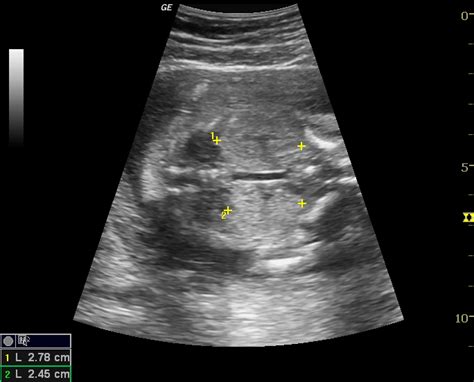

Swollen Kidney In Fetus

Web fetal hydronephrosis, or kidney swelling, occurs when too much urine backs up into an unborn baby’s kidneys. Web hydronephrosis occurs when the pelvis becomes enlarged because urine is collecting in the area of the kidneys. Web kidney swelling can result, causing the part of the kidney called the renal pelvis to bulge (distend), leading to. It can be a normal or abnormal condition during. Web hydronephrosis is a condition, affecting about 1 in 100 babies, where urine overfills or backs up into the kidney, causing the. Web hydronephrosis is the swelling of a kidney due to urine buildup in the urinary tract.